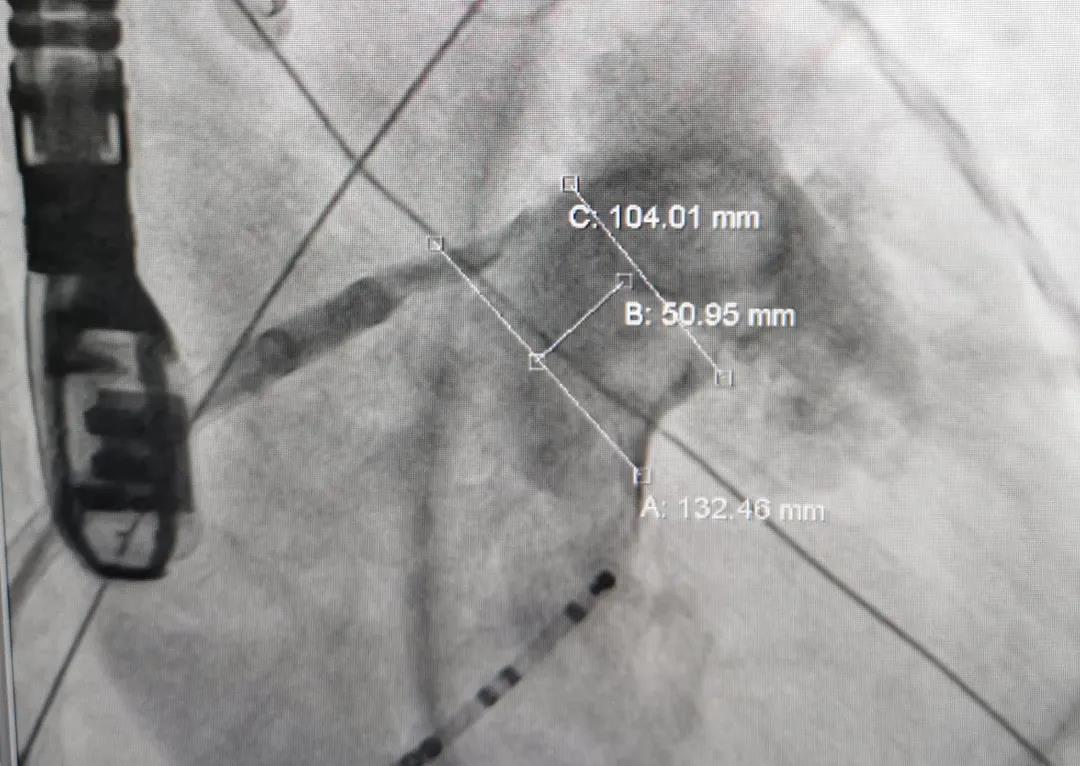

患者女性,71岁,因心慌气促20余天入院治疗,患有高血压及糖尿病史。多角度测量显示左心耳开口锚定区约为21mm,封堵区约为26mm,综合评估后选用LAmbre™2436封堵器,造影及食道超声显示无残余分流,患者术中、术后无不适,手术圆满成功。